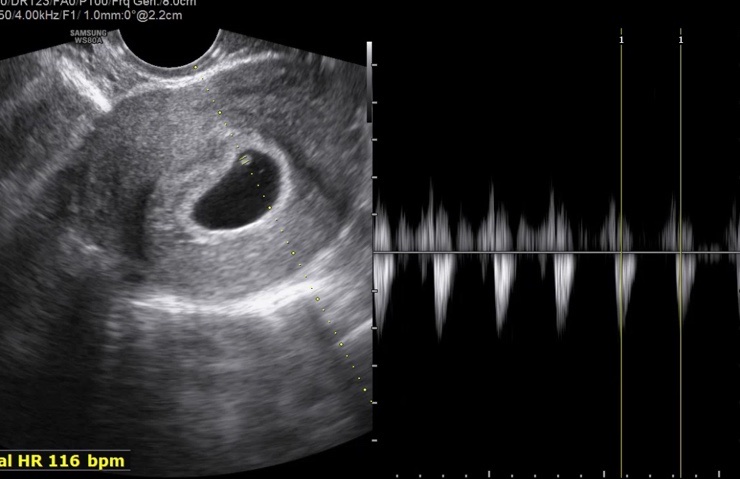

임신 5주차, 6주차 증상 산부인과 초음파

임신 5주차, 6주차 증상 산부인과 초음파 어플상 5주 6일에 산부인과에 처음 가는날!! 예약을 하고 갔고 기...